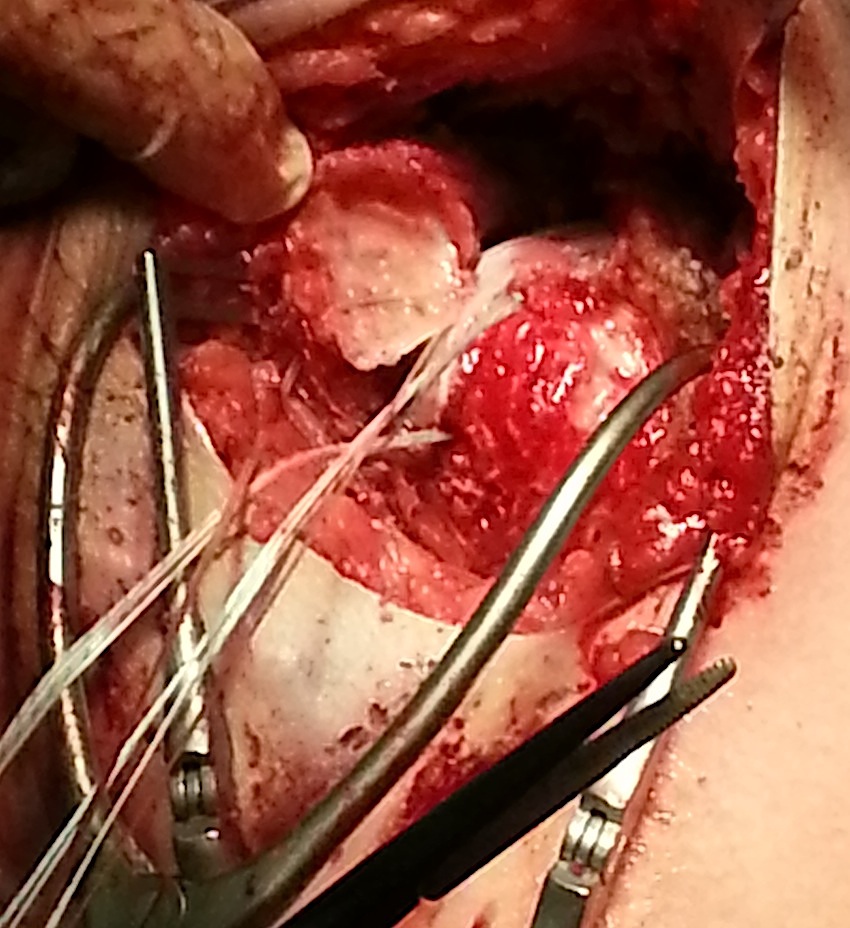

Open versus arthroscopic

Fixation methods

- screw fixation +/- soft tissue washer

- suture anchor + screws

- double row suture anchor fixation

Technique

JSES open fixation lesser tuberosity PDF

Arthroscopy techniques lesser tuberosity avulsion PDF

Screw fixation

Screw + soft tissue washer

Medial row anchors and lateral screws for missed lesser tuberosity avulsion in adolescent